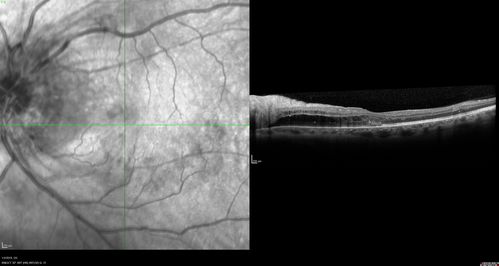

Grade 4 hypertensive retinopathy

55 year old man Hhe did have headaches a few weeks ago and also some nausea and vomiting.  He noticed for a few weeks the vision in the left eye was blurred and  that the vision in the left eye is dark.

VA OD: Dcc20/20

VA OS: Dcc20/100-1

He was admitted directly to ICU for blood pressure control (290 / 170 mmHg)

3 weeks later his VA increased to 20/20 OD, 20/32 OS